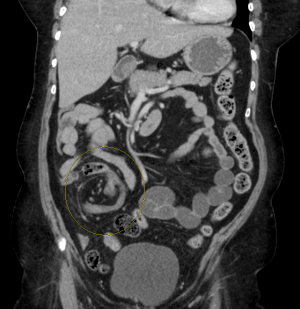

- CT

- Mesocolon "whirl sign"- twisted mesentery

- Cecal Volvulus

- "Coffee bean sign"-Large oval gas shadow with line down middle in middle of abdomen